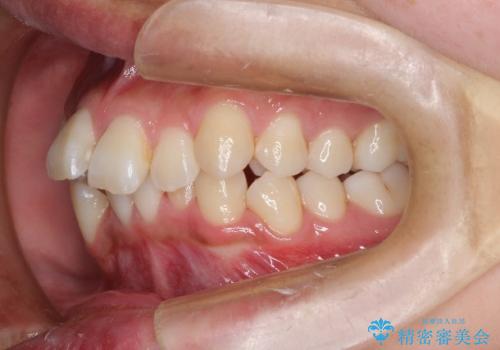

非抜歯で整える前歯の矯正

- 患者様は、前歯の重なり(叢生)が気になるとのことでご来院されました。診断の結果、奥歯を後方に移動することで前歯にスペースを確保し、非抜歯で歯列を整える方針としました。治療には審美性の高いホワイトワイヤーを使用し、奥歯の遠心移動にはリンガルアーチを装着しました。治療期間は約2年を予定し、月に一度の調整を通じて歯の動きを細かく管理しました。